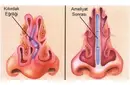

Kıkırdak dokunun kendini yenileme özelliğinin az olması, maalesef eklem sağlığı açısından ciddi sorunlar yaratabilir. Kıkırdak dokusu, eklemlerimizin düzgün hareket etmesini sağlar ve bu dokunun zarar görmesi, ağrı, sertlik ve hareket kısıtlılığı gibi problemlere yol açabilir.

Kıkırdak dokusunun hasar görmesi durumunda uygulanabilecek çeşitli tedavi yöntemleri bulunmaktadır. Bu tedaviler arasında fizik tedavi, ilaç tedavisi (ağrı kesiciler ve anti-inflamatuar ilaçlar), enjeksiyonlar (kortikosteroid veya hyaluronik asit) ve ileri vakalarda cerrahi müdahaleler yer alabilir. Cerrahi tedaviler arasında artroskopi, mikrokırık cerrahisi ve kıkırdak nakli gibi yöntemler bulunur.

Tedavi seçenekleri, kıkırdak hasarının derecesine ve hastanın genel sağlık durumuna göre değişiklik gösterebilir. Bu nedenle, bir ortopedi uzmanına danışarak en uygun tedavi planını belirlemek önemlidir.